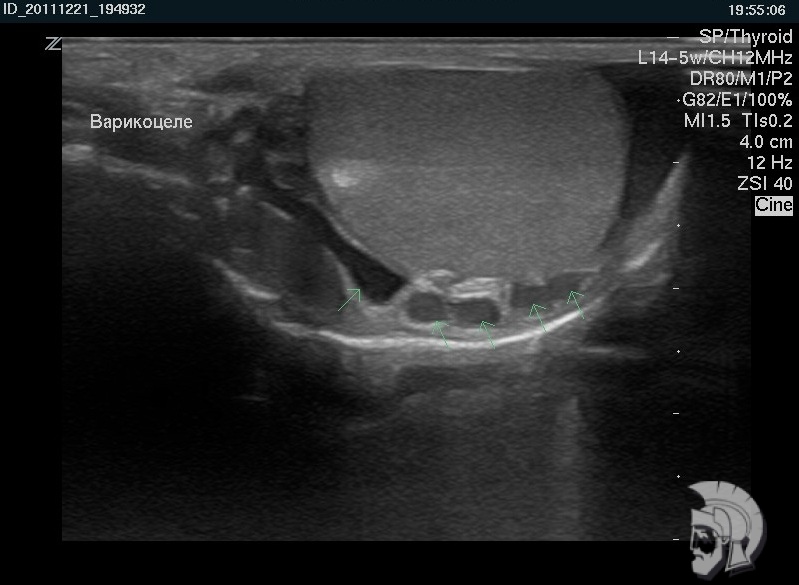

| Фото варикоцеле. Расширение вен семенного канатика (варикоцеле) у мужчины 29 лет |